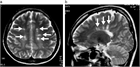

1. MRIのSTIR法は、視神経炎の病態把握に有用で推奨される(推奨度1)

1. 視神経炎の活動性炎症の有無はMRIのT1強調画像脂肪抑制造影で判断する(推奨度1)